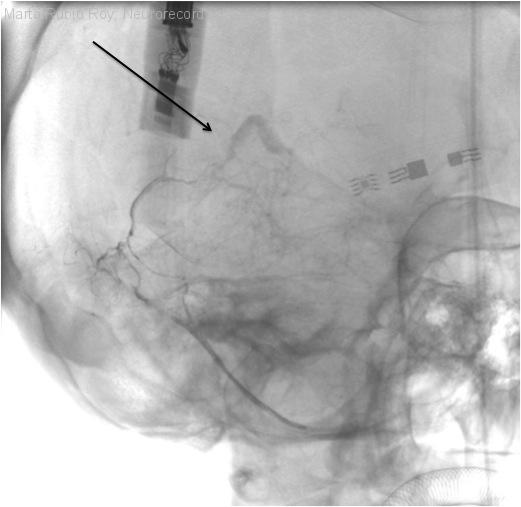

Mutismo acinético por trombosis venosa cerebral profunda

Diagnóstico final: Trombosis venosa cerebral profunda causada por fístula arteriovenosa

Neurología: Patología cerebrovascular

Etiología: Malformación vascular